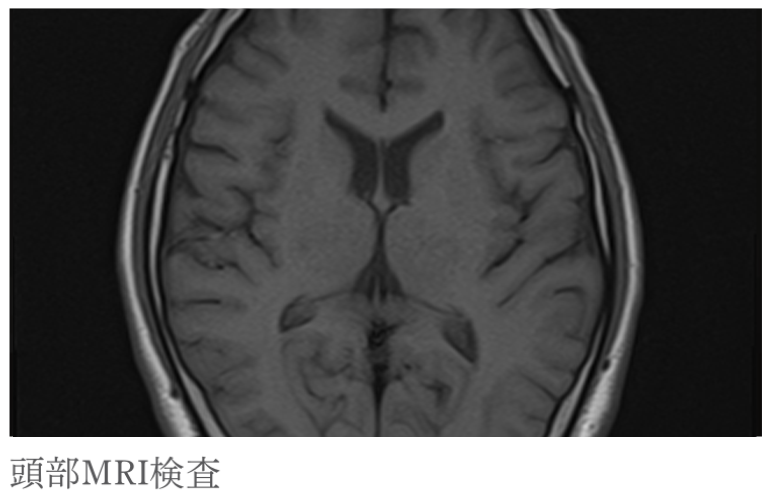

・頭部MRI検査

骨に邪魔されることなく、CTよりも鮮明な画像が得られるため、脳梗塞の早期診断に有効です。